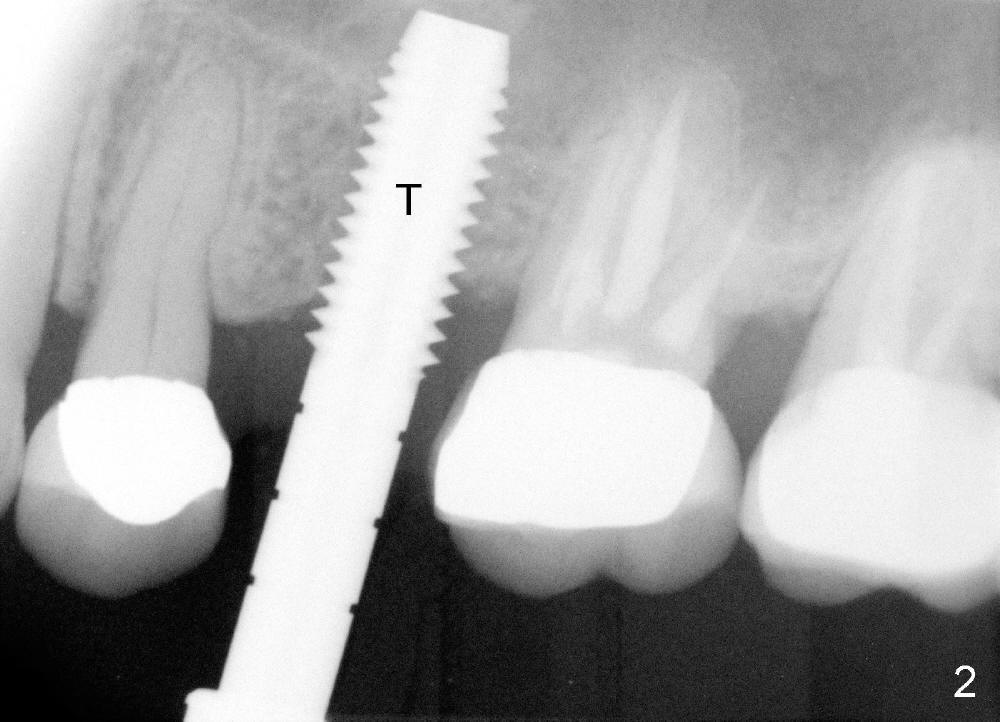

A 59-year-old lady used to have a 3-unit bridge in the upper left quadrant. A 4.5x6mm Bicon implant (Fig.1 B without extruding into the sinus) was placed in the atrophic pontic area 5 months earlier. When the abutment (A) was removed, the implant came out. The osteotomy was processed with a 4.5x14 mm tapered tap, which was unstable. When a 4.8 mm cylindrical tap was placed (past the sinus floor), it was tight (Fig.2). A 5x14 mm cylindrical implant (Fig.3 I) was inserted with elevation of the apparent sinus floor (>, no allograft used in case of sinus infection). Seven months postop, the density of sinus floor increases (Fig.4 <). The implant is stable and processed for crown (Fig.5 C, different view of the lifted sinus floor (<)). While sinus floor density is decreasing, the mesial and distal bone density is increasing 6 months (Fig.6), 1 year 6 months (Fig.7) and 3 year 6 months (Fig.8) post cementation.